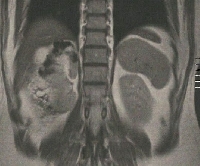

Δεξιά ηπατεκτομή (σωστική παρεγχύματος, parenchymal sparing) και δεξιά νεφρεκτομή για εχινοκοκκίαση

Πρόκειται για ασυμπτωματικό άνδρα ασθενή 54 ετών που υποβλήθηκε σε υπερηχογράφημα άνω κοιλίας στα πλαίσια προληπτικού ελέγχου, το οποίο ανέδειξε πολύχωρη εξεργασία του ήπατος. Ακολούθησε MDCT και MRI, κατά την οποία διαπιστώθηκε η ύπαρξη ηπατικής (CE3b) και νεφρικής (ΔΕ) εχινοκκοκίασης (εικόνες 1 & 2). Ο ασθενής έλαβε προεγχειρητική χημειοπροφύλαξη με albendazole για 4 εβδομάδες. Υποβλήθηκε σε δεξιά ηπατεκτομή (σωστική παρεγχύματος) και δεξιά νεφρεκτομή (εικόνες 3 & 4). Τα παρασκευάσματα φαίνονται στην εικόνα 5. Έλαβε εξιτήριο την 7η μετεγχειρητική ημέρα.